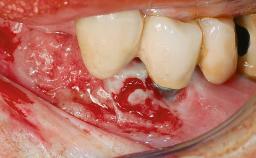

A 30-year-old female patient was referred to the Department of Periodontology of the University of Bern, Switzerland, by a dentist in private practice. Tooth 45 had been congenitally missing and had been replaced with a titanium implant three years prior to the first visit at the Department of Periodontology. The tissue level implant had a diameter of 4.1 mm, a length of 12 mm, and a sandblasted and acid-etched (SLA) surface (Straumann® Dental Implant System; Institut Straumann AG, Basel, Switzerland). The metal-ceramic crown on implant 45 had been cemented permanently. Implant 45 had been diagnosed with peri-implantitis by the referring dentist in the course of regular supportive care.